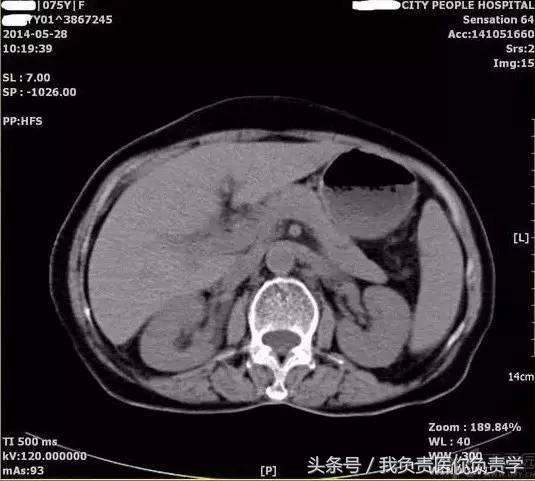

典型病例 5

(由丁香园注册用户「ouchen2010」提供)

患者女,75岁,右上腹疼痛就诊。查体示右上腹压痛明显,无明显腹膜炎体征。

超声检查发现胆囊内可见沉积物及结石回声,胆囊近底部可见 0.5cm 回声中断,十二指肠亦可见 0.5cm 回声中断,二者间见 5.8×4.4cm 混合性团块。

图1示胆囊饱满,内透声差,可见沉积物回声

图2示胆囊、胃窦及十二指肠之间可见混合回声型团块

图3-图5为胆囊局部放大图像,显示胆囊囊壁局部回声中断,周围可见不规则混合回声团块

图6和7为相应CT表现

术后诊断为慢性结石性胆囊炎,胆囊-十二指肠穿孔并内瘘形成。